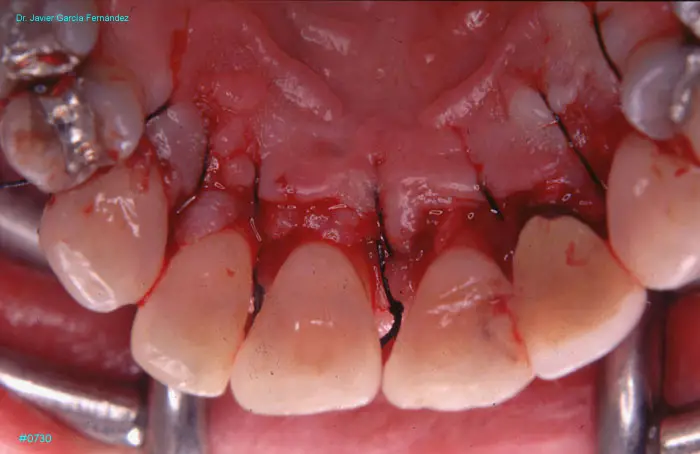

Atlas of Surgical Techniques in Periodontics. Chapter III. Atlas de Técnicas Quirúrgicas en Periodoncia